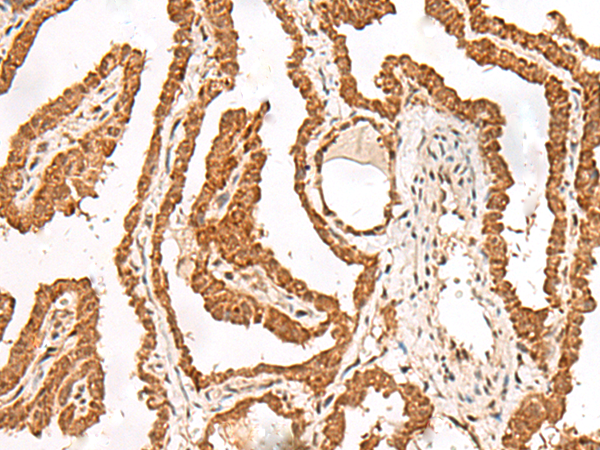

FER |

The protein encoded by this gene is a member of the FPS/FES family of non-transmembrane receptor tyrosine kinases. It regulates cell-cell adhesion and mediates signaling from the cell surface to the cytoskeleton via growth factor receptors. Alternative splicing results in multiple transcript variants. A related pseudogene has been identified on chromosome X. |

IHC positive control: |

Human esophagus cancer and Human thyroid cancer |